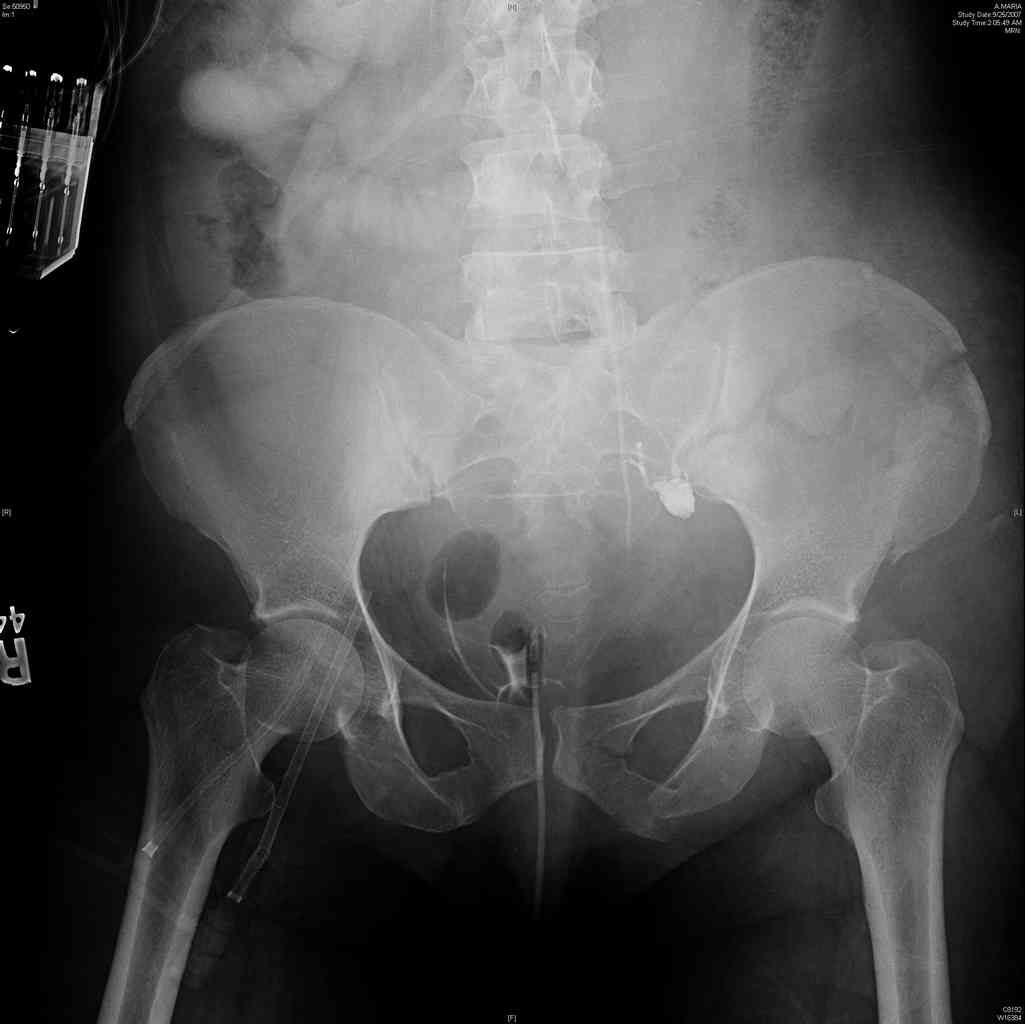

[Ortho] comminuted crescent fx

Any advice would be appreciated:

40 ish female ejected from car. Unstable, DPL negative, went to angio and had her pelvic bleeds embolized after many units of blood. GCS 6, floating elbow, clavicle, bothbones, etc.

My standard approach to  this pelvis would be posterior, reduce/lag/plate  thecrest, reduce/plate the caudal extent on the posterior crest and 1-2 lags back to front. In this case, the crest comminution seems to make plating all

the way to the ASIS useless, as the plate would be on free floating fragments. Would plating the posterior extent of the fracture to secure the

reduction at the SI joint and 2 screws back to front be sufficient fixation? Would anyone do a perc reduction and perc back to front screws, and would that be sufficient if the SI joint could be reduced (although I don't see how this could be accurately reduced closed). Would an ilioninguinal with a pelvic brim plate and posterior column screws be a better approach, although reducing the SI would be more indirect and less accurate?